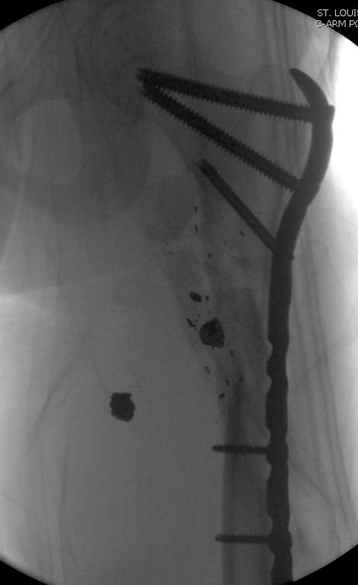

Re: [3/3] Перелом проксимального бедра

Молодой, с общим состоянием без проблем. Больной соперирован в день поступления и через два дня после операции выписан, так что не успел развиться гной.

Перелом низкоскоростным оружием, типа пистолетного, так что не стали гоняться за пулевыми фрагментами. С нервом пока подождем, иногда нерв восстанавливается если не прямое попадание в нерв, а "сотрясение" (shock wave injury).

Из всех типов фиксации взяли малоинвазивную технику мостовидной пластиной, использовали Locking проксимальную Synthes пластину.